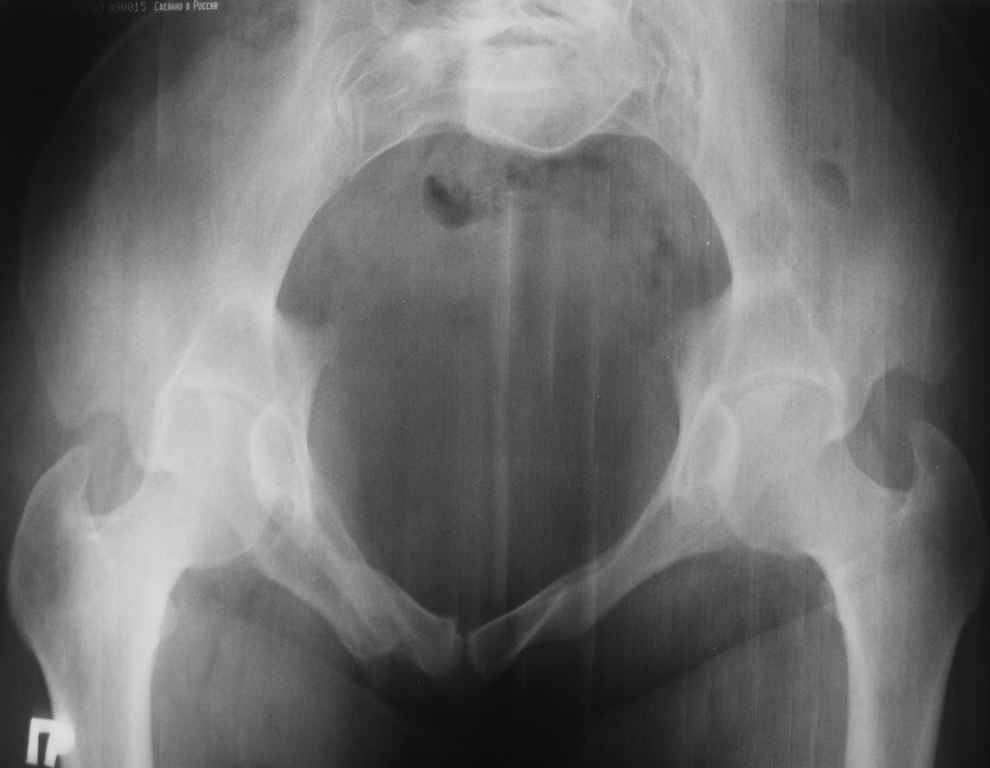

13/03/03 |  13/03/03 |  13/03/03 |  15/09/06 |  15/09/06 |  07/03/07 |  07/03/07 |  19/12/06 | К нам в клинику поступила пациентка 30 лет с диагнозом: Постравматическая ротационная стабильная деформация тазового кольца. Относительное укорочение левой н\конечности на 1 см. Левосторонний компенсаторный сколиоз 2 ст. Болевой синдром. травма автодорожная в январе 2003г. Пассажирка переднего сидения ваз 2109. лечились положением по Волковичу. С марта 2003 года жалуется на боли в тазу, ппояснице усиливающиеся при движении.В настоящее время жалобы на боли в области крестца, КПС больше слева, в пояснично-крестцовом отделе позвоночника. неприятные ощущения, щелчок при выпрямлении правого тазобедренного сустава из положения полного сгибания. боли в тазу появляются при ходьбе ч\з 100 м, так же при вставании из положения сидя, после сидения в течении 2-3 часов. при ходьбе более 100 м появпяется зябкость стоп больше справа. ходит при помощи трости в правой или в левой руке. без трости боли появляются сразу после начала ходьбы. пальпация болезненна в паравертебральных точках средне-грудного и пояснично-крестцового отделов позвоночника, КПС с обеих сторон. Объем движений в тазобедренных суставах полный.правый КПС заблокирован. симптомы натяжения с обеих сторон отрицательны.С 2003г. лечится консервативно, получала ЛФК, массаж, физиолечение - без эффекта. в 2005г. лечилась в санатории с ортопедическим уклоном, получала плавание в минеральной воде, магнитотерапия, массаж, ЛФК. отмечала умеренное улучшение в течении 2 недель.Вопросы:надо ли оперировать, т.е. устранять относительное укорочение левой н\конечности и как?Если не оперировать, то как лечить консервативно?Р-граммы, КТ прилогаются.

Проблема Вашей пациентки находится на границе интересов специальностей ортопедия (вертебралогия) и неврология (нейрохирургия), вероятно, поэтому так мало откликов на ваше обращение. Представленные рентгенограммы не все информативны (особенно спондилограммы от сентября 2006 года). Вероятно, необходимы дополнительные методы исследования к.т. МТГ, ЯМРТ, миелография.

Уважаемый Алексей. Описанные Вами клинические проявления указывают на нестабильность левого крестцово-подвздошного сочленения. Такие больные встречаются не редко (за последние 6мес.в нашей клинике оперировано 3 больных со сроками давности от 6мес. до 1 года). К сожалению рентгенологически их трудно обьективизировать. На КТ это проявляется артрозом и костными разрастаниями КПС. В Вашем случае рентгенограммы и представленные томограммы ничего не дали. Можно попробовать посмотреть связочный аппарат КПС на МРТ хотя не уверен что Вы получите окончательный ответ. Если Вы будете убеждены в этом диагнозе то выход один костно-пластический артродез левого крестцово-подвздошного сочленения с фиксацией канюлированными шурупами. Заманчиво конечно и устранить ротационное смещение половины таза, но это на Ваше усмотрение.

почему она должна возникнуть? Сломан вроде крестец, хотелось бы посмотреть функциональные снимки таза.

Уважаемый Максим. Снимки от 7.03.07 и есть функциональные, т.е. стоя на правой, и левой ноге.